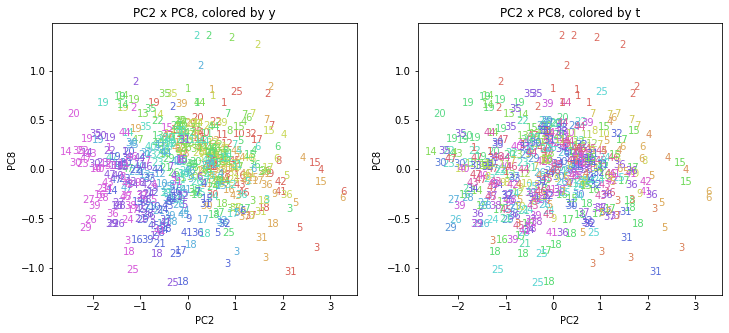

PCAの結果の第n主成分をPCnと表記します。

医療費データの場合と同様に、PCAの結果を見やすく表示するため、seabornのカラーパレットを使って、年月別、都道府県別に色分けして図示してみます(左側が年月別に色分け、右側が都道府県別に色分け)。PC1~PC8まで表示しました。

都道府県番号の表示

上の色分けだけでは都道府県が区別しにくいので、医療費データの場合と同様に、点の代わりに都道府県番号をプロットした図も描いておきます(色分けは上と同じ)。

医療費データの場合ほどはっきりとはしていませんが、PC2が概ね時間の経過を表す成分で、残りの成分が時点によって変わらない地域の特徴を表す成分となっているようです。

また、PC1×PC3を見ると、47沖縄が他の都道府県からかなり離れたところに位置しており、沖縄の地域差が際立っているのが分かります。これは、以前別の記事で年齢階級のない健診データでPCAを実行した場合と似た結果となっています。

今回は、医療費データと同様に、健診データ240次元についてPCAを実行してみました。PCAの結果、医療費データの場合ほどはっきりしとはしていませんが、第2主成分が概ね時間の経過を表す成分で、時間軸に沿った全体的な動き(全国的な動き)を表しており、それ以外の成分が地域の特徴を表す成分で、この10年間あまり変わっていないことがわかりました。